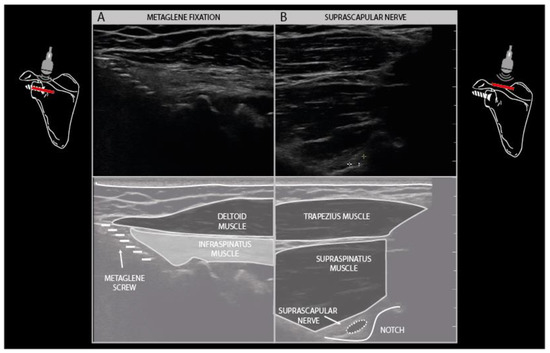

Another common finding is the presence of osteosynthesis material in the vicinity of the injured nerve. Fixation plates and screws and K-wires can usually be visualized with ultrasound as hyperechogenic edges and structures that cover or pierce a bony cortex in the vicinity of the nerve (Figure 7F). It is well known that the placement of osteosynthesis material for certain indications poses a risk to peripheral nerves in that area, such as the radial nerve during humeral shaft fixation, the suprascapular nerve during metaglenoid fixation in reversed total shoulder arthroplasty, and the ulnar nerve during temporary elbow fracture fixation (Figure 13).

Figure 13.

Reverse shoulder arthroplasty with metaglene fixation screw traction injury to the suprascapular nerve. Hyperechogenic, denervated infraspinatus muscle layer underneath a normal appearing deltoid muscle (A). Suprascapular neuroma in continuity (3× normal size) at the level of the spinoglenoid notch (B).

Sometimes it is not the osteosynthesis or prosthetic material itself that poses the risk, but the approach the surgeon must take to get the material in place. Hip joint replacement surgery is notorious for its risk of traction damage to the fibular part of the sciatic nerve, when the hip joint has to be bent open to insert the prosthetic shaft and ball and the cup part of the prosthesis [10]. As the fibular part of the nerve is fixed by the biceps femoris tendon insertion in the proximal part of the lower leg, traction on the sciatic nerve produces the greatest tensile stress on this part of the nerve, leading to injury in about 5% of patients having their primary surgery.